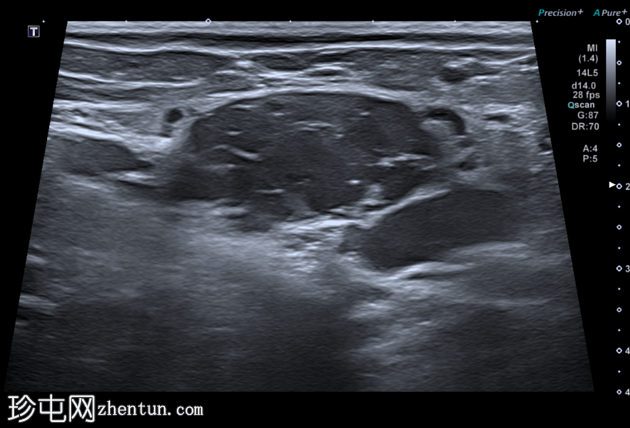

横切面

超声显示一个卵圆形低回声肿块,内部有多处分隔,与腹膜内脂肪不符,且未见蠕动(提示肠袢疝出)。

B超显示该结构内血流缓慢。

虽然本次图像未达到最佳效果,但彩色多普勒显示内部血流信号增强,Valsalva动作后血流信号增加,证实该结构为静脉性质。